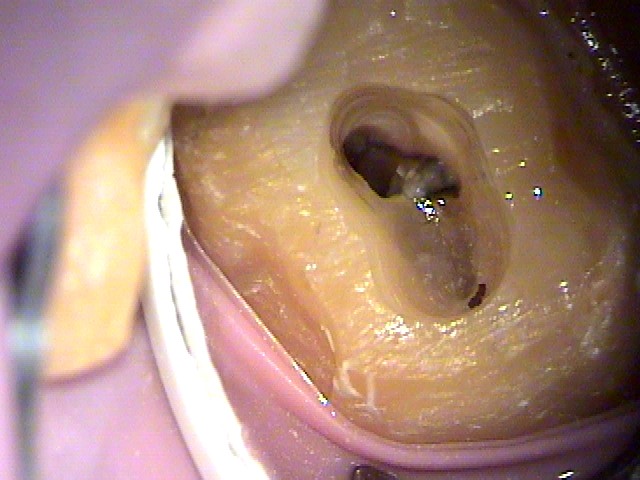

麻酔後にラバーダム防湿を行い、随腔内(歯の神経の入っている空間)を観ると破折線のような物も確認する事ができます。

随腔内は健全な歯髄は確認できず、腐敗して溶けかかっているように観えます。

歯髄は、溶けかかっているため、マイクロバキュームで一部を吸い上げる事ができます。